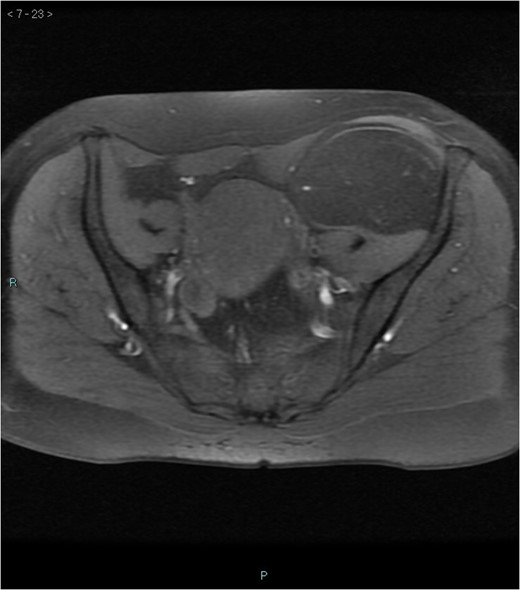

A 58-year-old woman was evaluated for lower abdominal pain, without additional symptoms. An abdominal ultrasonography revealed the presence of a 15 cm homogenous mass, located in the left pelvic cavity. Subsequent MRI showed a capsulated mass, isointense with the adipose tissue, longitudinally extending from the left inguinal area to the left leg root and located on the medial aspect of the left iliac bone. MRI also revealed within the mass some fibrotic branches containing small blood vessels. No evidence of extracapsular invasion of the surrounding structures was evident (Figs 1–6).

Preoperative differential diagnosis is mainly based on radiologic imaging and is very difficult, because no pathognomonic signs exists for diagnosis of hibernoma; usually CT-scan shows an homogenous lesion, whose density is between subcutaneous fat and skeletal muscle; MRI shows slightly lower signal intensity on T1 weighted spin-echo (T1WSE), marked enhancement and partial fat suppression on short Tau inversion recovery (STIR) and fat-saturated sequences [5].